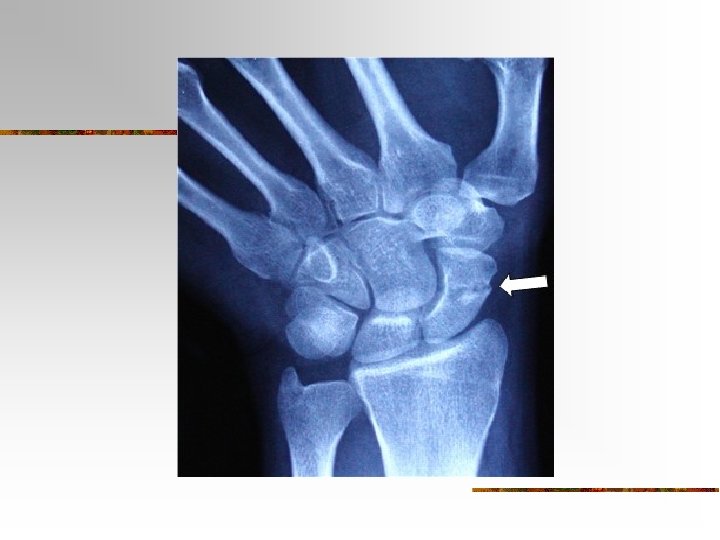

Carpus (Wrist) n n 8 carpals Held together by ligaments with four bones in each row Named for their shapes Short bones

n The carpals in the proximal (closest to the radius/ulna) row are the: n Scaphoid, Lunate, Triquetrum, and Pisiform n The carpals in the distal row are the: n Trapezium, Trapezoid, Capitate, and Hamate

Fractures